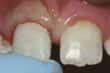

Et stort stykke av en fortann er slått av

En tann hvor et lite stykke er brukket av - Hvis du ikke har vondt og det manglende stykke er lite, haster det ikke med å oppsøke tannlege. I mange tilfeller kan den oppståtte ujevnheten fjernes med en lett avpussning. Er skaden litt større og kosmetisk uheldig kan den repareres med en plastfylling. La tannlegen vurdere optimal behandling. Hvis det manglende stykke stammer fra en fylling, vil ofte hele fyllingen legges om/revideres.

Sprukket eller brukket tann - Sprukkede eller brukkede tenner skal repareres så fort som mulig for å hindre ytterligere skade. Det kan være nødvendig med rotbehandling eller å trekke tannen, hvis skaden er omfattende. Å legge en krone kan ofte være den beste behandlingen. Sprekker er ikke alltid synlige - heller ikke på røntgenbildet. Men du kan merke de ved smerte når du tygger, og ising i tennene når du inntar kalde eller varme mat- og drikkevarer, eller eksponering for kald luft, er vanlig.